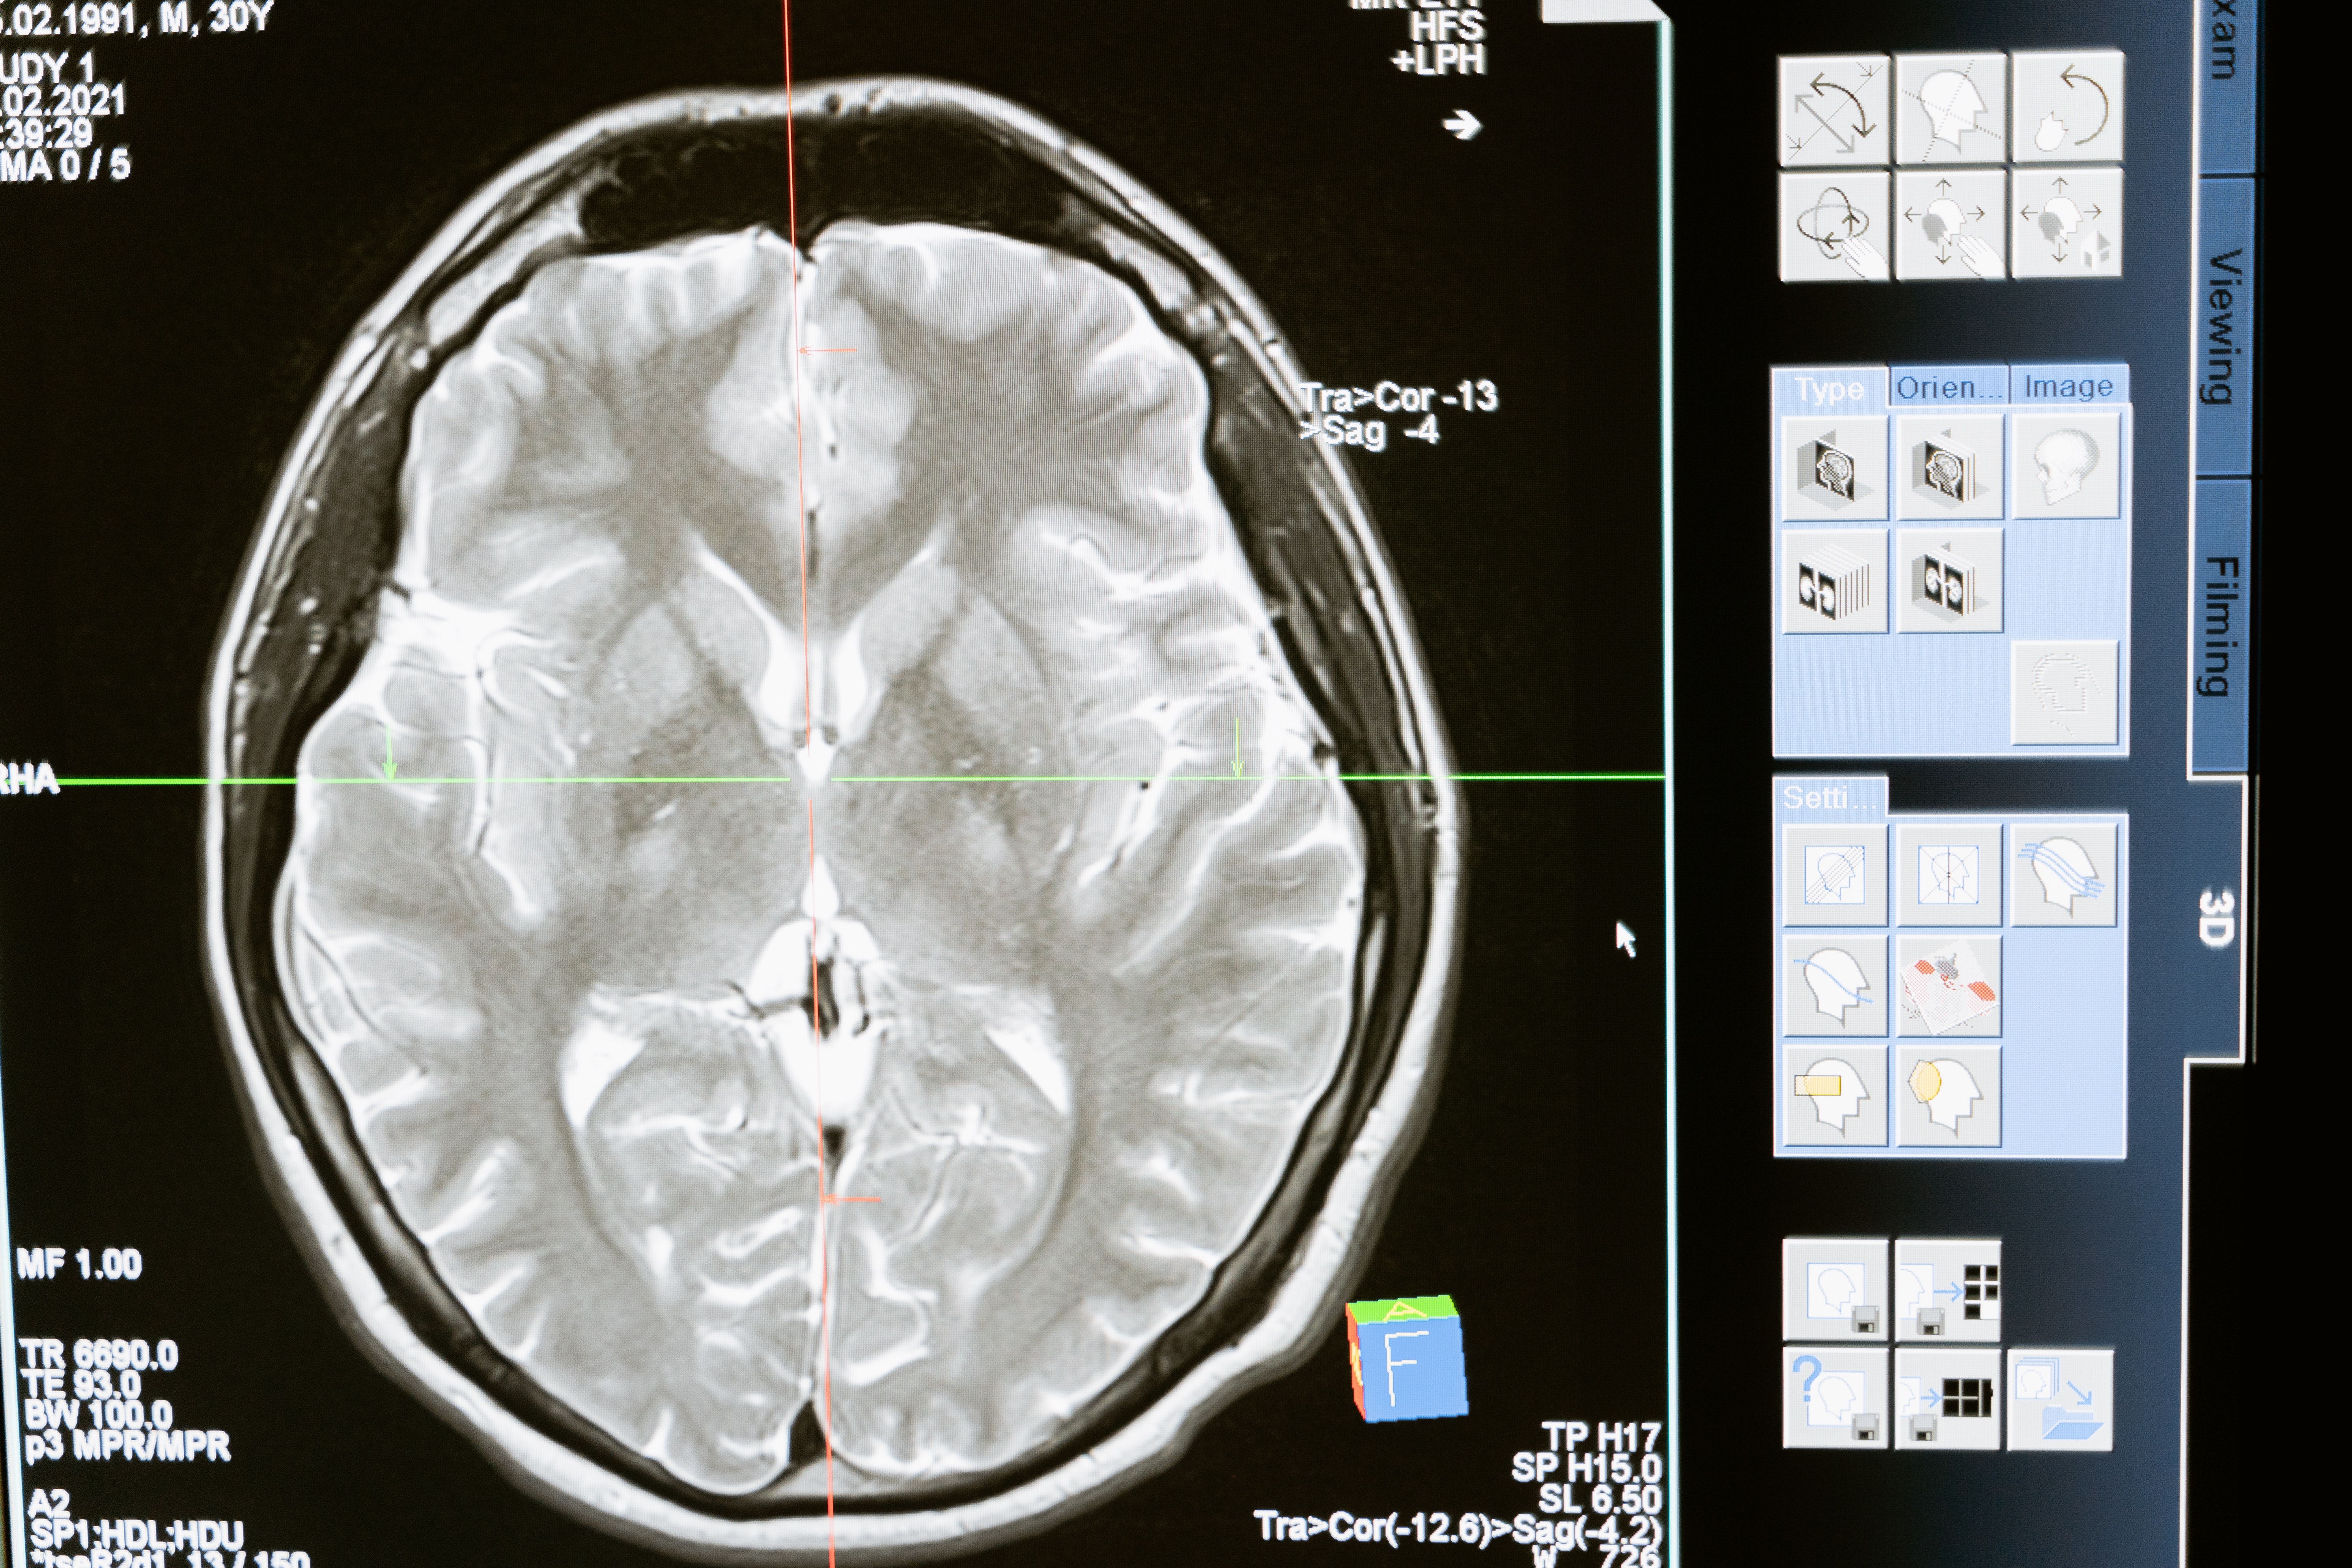

뇌질환은 크게 세 가지로 구분됩니다. 첫 번째, 뇌출혈. 두 번째, 뇌출혈을 포함한 뇌졸중. 그리고 세 번째 뇌졸중을 포함한 뇌혈관질환을 말합니다. 건강보험심사평가원의 통계자료에 따르면, 뇌출혈 환자수가 뇌혈관질환에서 차지하는 비중이 10% 내외이고, 뇌 졸중이 뇌혈관질환에서 약 66%를 차지합니다.

뇌의 무게는 우리 몸의 2%밖에 차지하지 않지만, 허파로 들이마시는 산소의 20%, 심장이 펌프질 하는 혈액의 15%를 사용한다고 합니다. 그래서 중추기관으로 불립니다.

뇌출혈은 혈관 벽에 갑자기 높은 압력이 가해져 터지는 것을 말합니다. 뇌출혈은 크게 두가지고 나뉩니다. 뇌 안에서 터지느냐? 혹은 지주막(거미막)에서 터지느냐입니다. 강수연 씨의 사인은 뇌 안에서 터져서 발생한 뇌 내출혈(I61)입니다.

뇌 내출혈이란 혈압으로 인해 뇌 안에 미세혈관들이 터졌을 때 나타납니다. 즉, 실핏줄이 머릿속에서 터지는 것을 말합니다. 실핏줄이 터지는 대부분의 이유는 그 작은 혈관이 혈관의 압력을 못 이겨서 발생합니다. 즉 뇌내출혈의 대부분의 원인은 고혈압입니다.